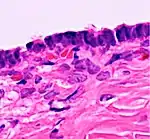

Histopathology

In case an ovarian cyst is surgically removed, a more definite diagnosis can be made by histopathology:

| Type | Subtype | Typical microscopy findings | Image |

| Functional cyst | Follicular cyst |

|